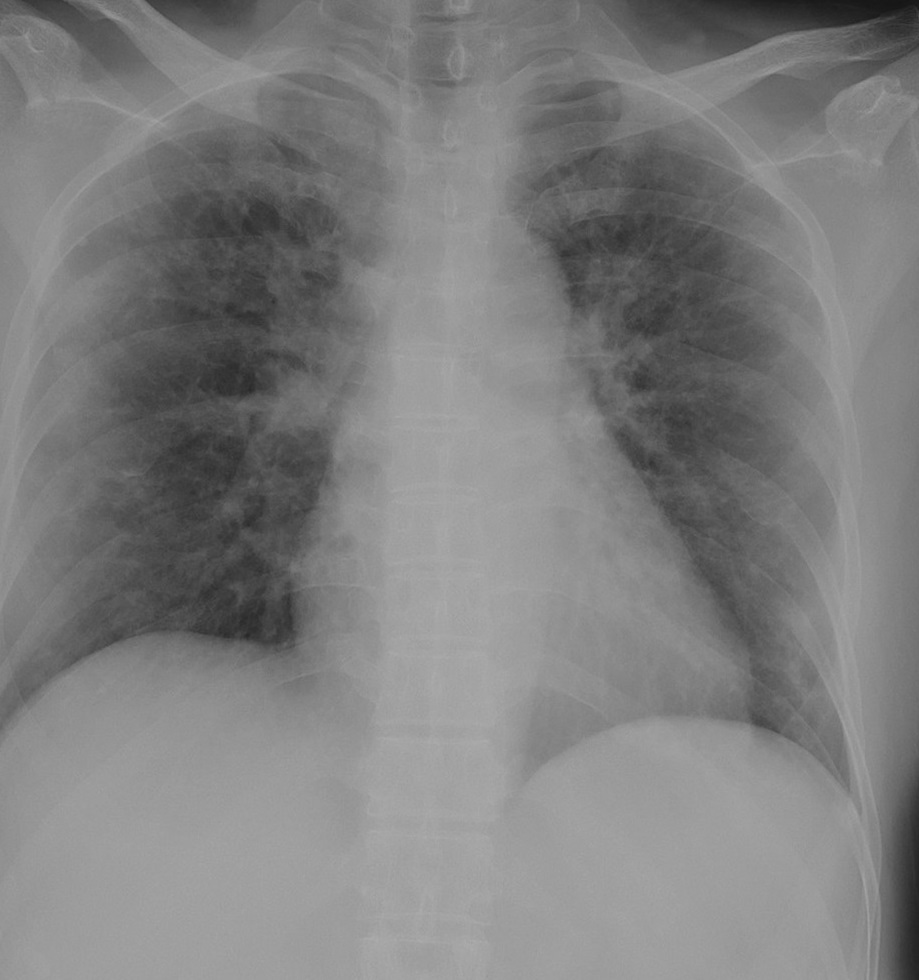

Figure 6 presents image examples for each class retrieved from the RYDLS-20 database. It is worth to mentioning that we have no further information concerning the CXR images with regarding the CXR machine used to take the image, as well as the origin, age and ethnicity of the people whose these images belong to.

Refer to caption

(a) Normal.

(b) COVID-19.

(c) SARS.

(d) MERS.

(e) Pneumocystis.

(f) Streptococcus.

(g) Varicella.

Figure 6: RYDLS-20 image samples.